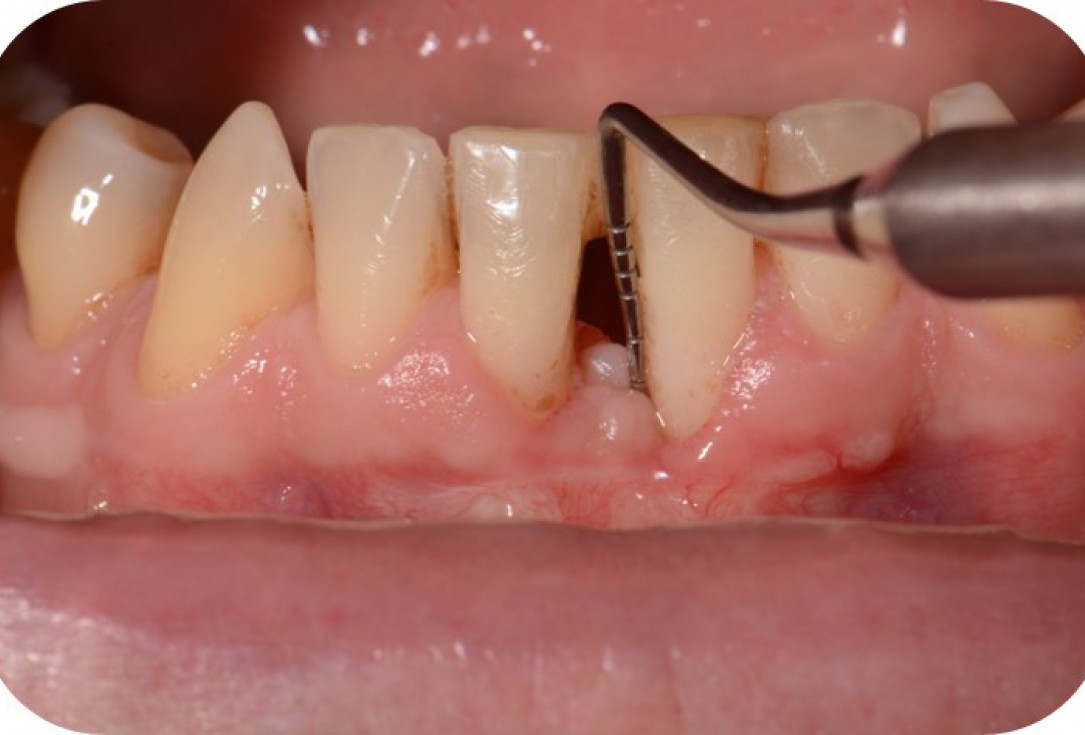

11/12 - Clinical situation 6 months post-operative.Two-wall intrabony defect treated using cerabone® and Straumann® Emdogain® - Dr. D. Rakasevic & Prof. Dr. S. Jankovic